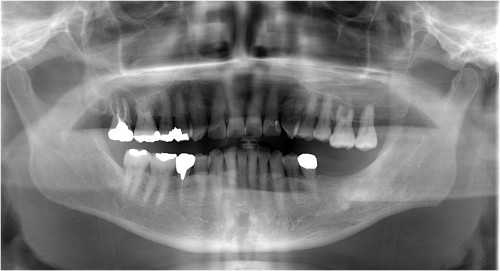

インプラント 右上4567 川口で精密インプラントなら さかえ歯科

2017年02月2日